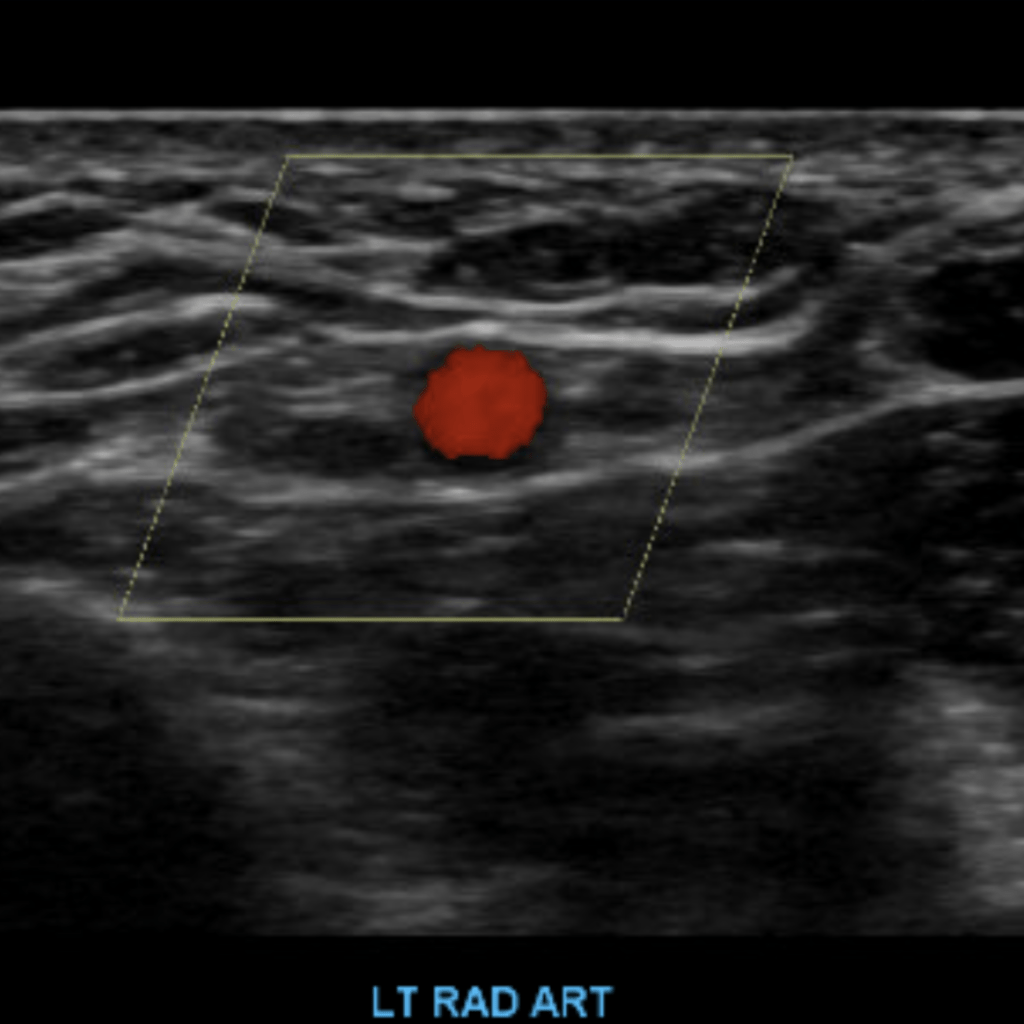

The subclavian artery arises from the brachiocephalic artery on the right and off of the aortic arch on the left. This artery further divides into the axillary, brachial, radial, ulnar, palmar and digital arteries respectively.